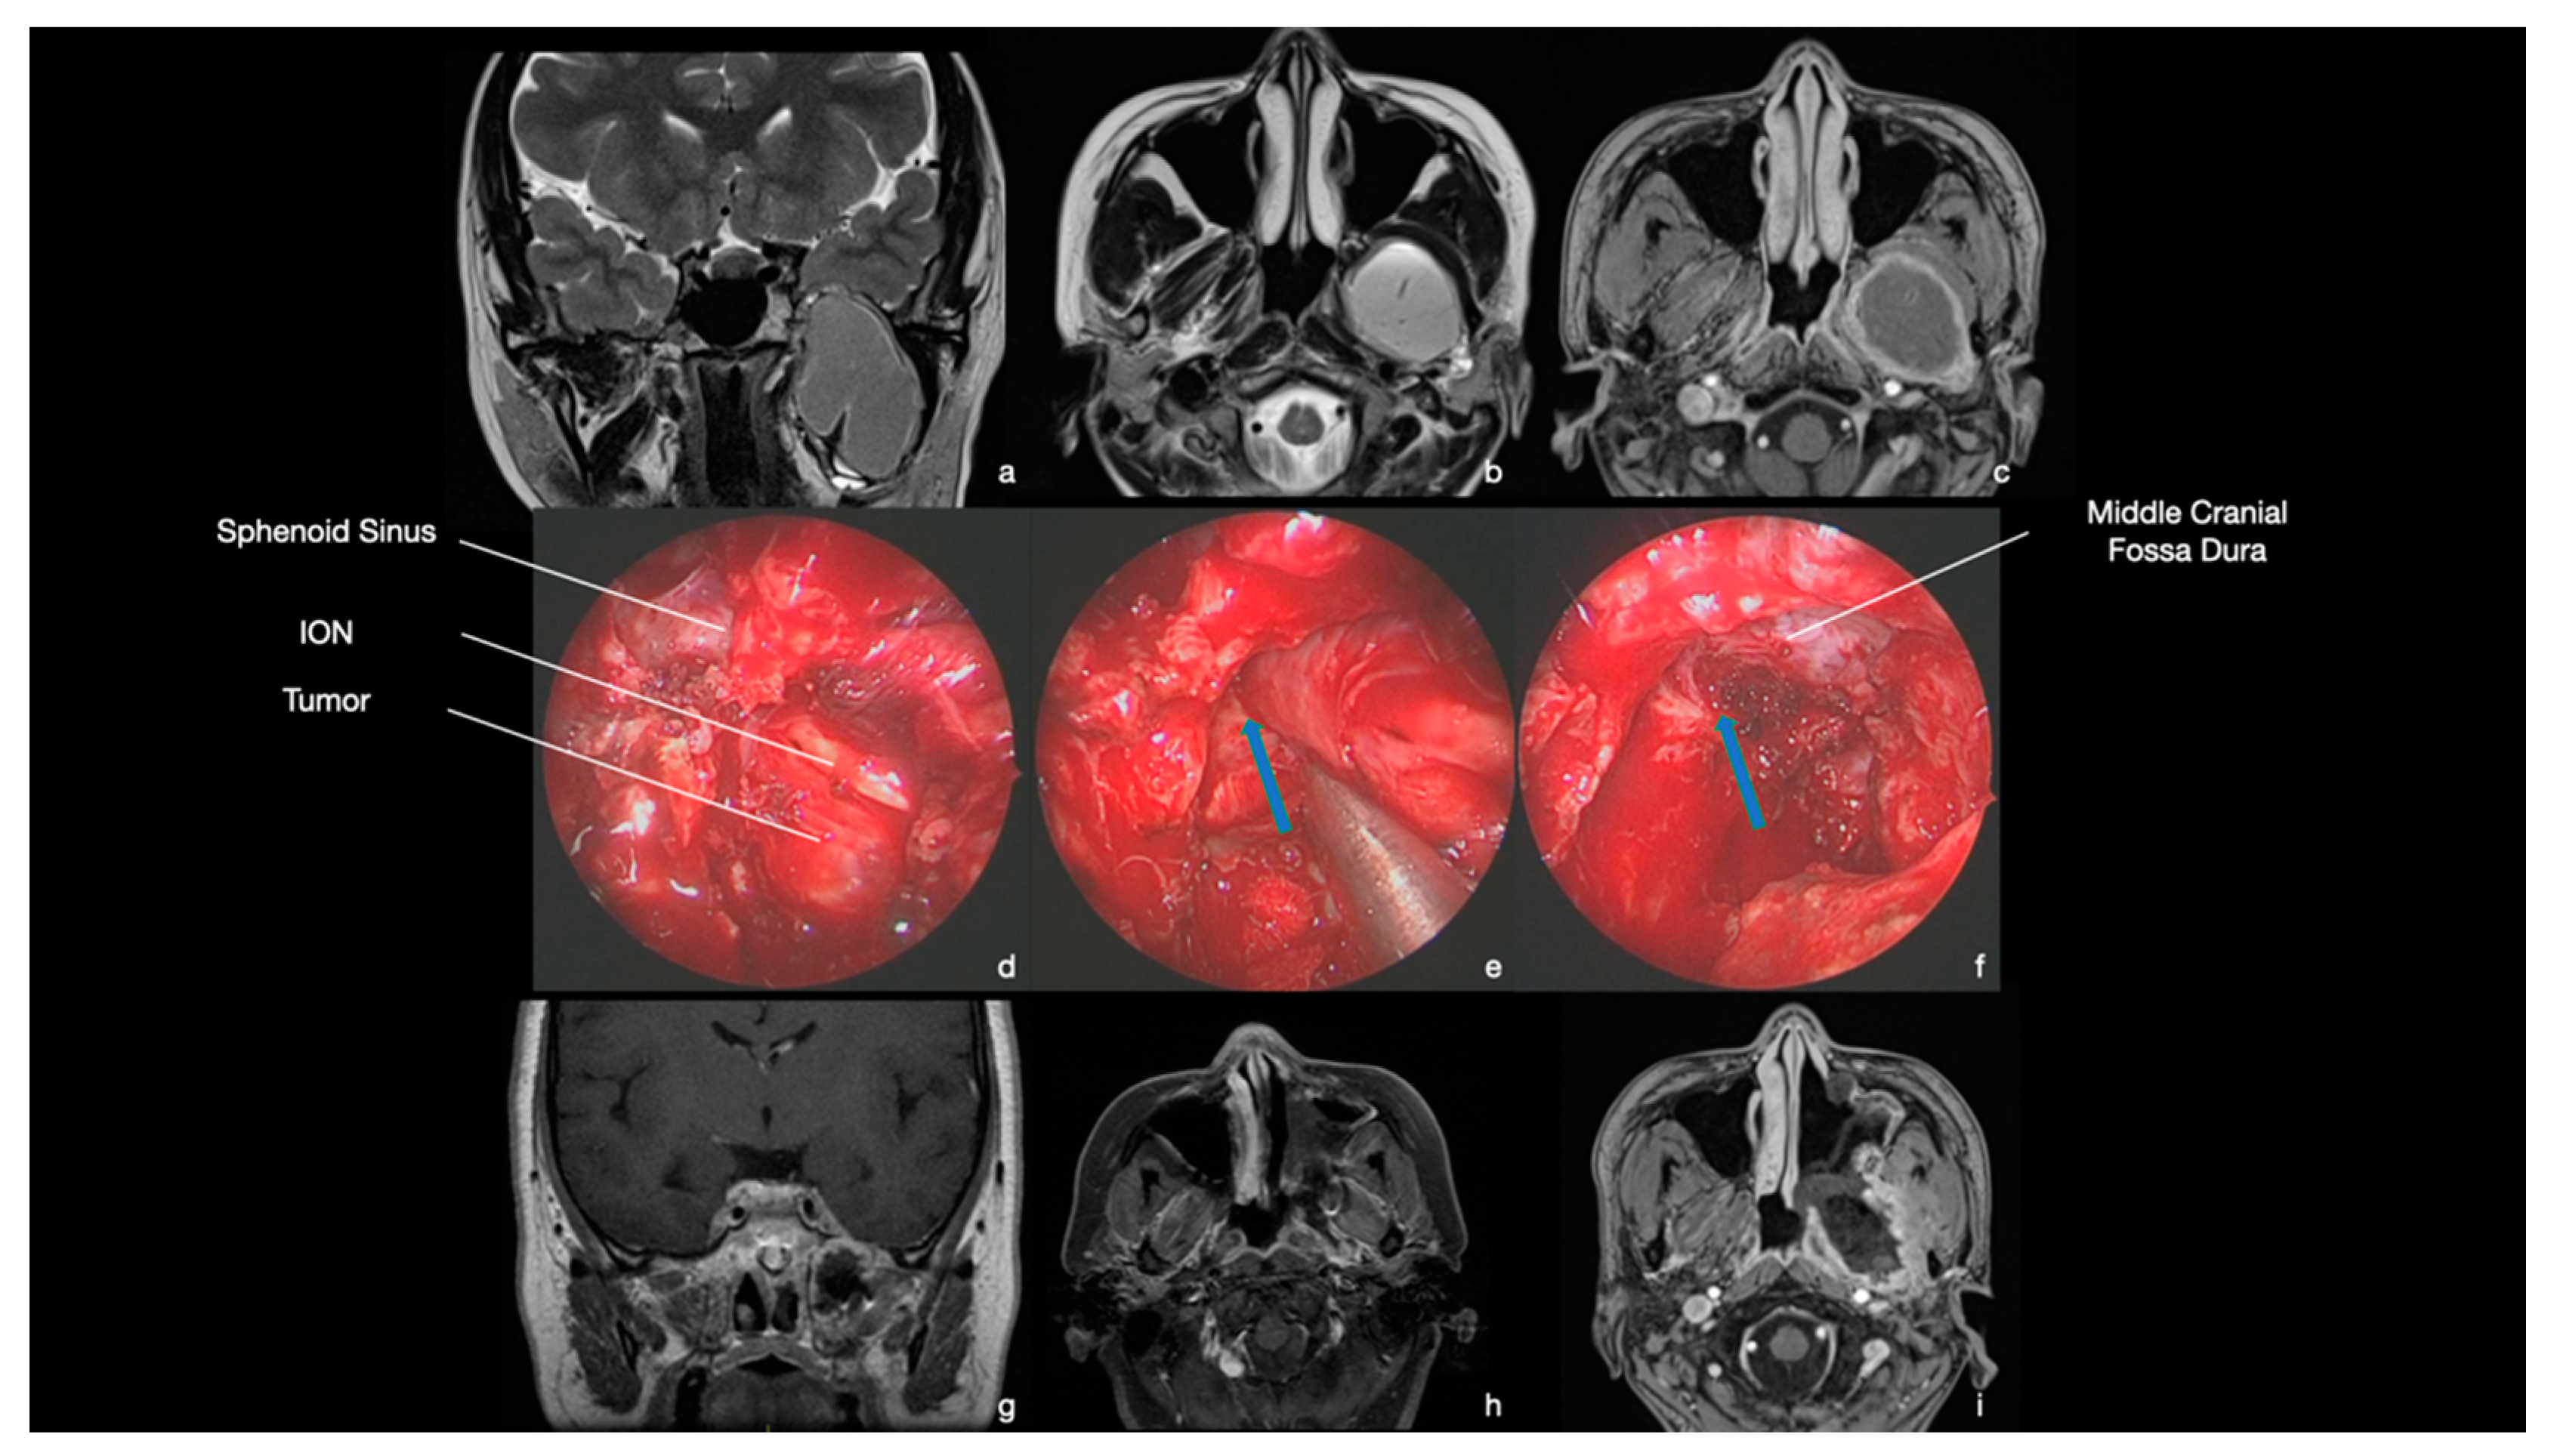

9.3. Case 3